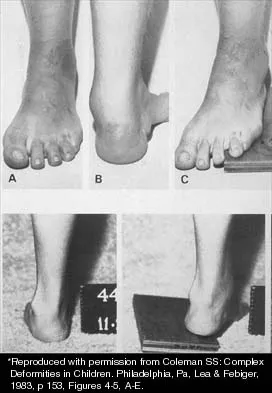

A 15-year-old boy with a type I hereditary sensory motor neuropathy (Charcot-Marie-Tooth disease) reports recurrent ankle sprains and significant pain in the hindfoot and midfoot despite orthotic management. Examination reveals that he walks with a drop foot and has dynamic clawing of the toes. Clinical photographs of the left foot are shown in Figure 7. Management should consist of

Explanation